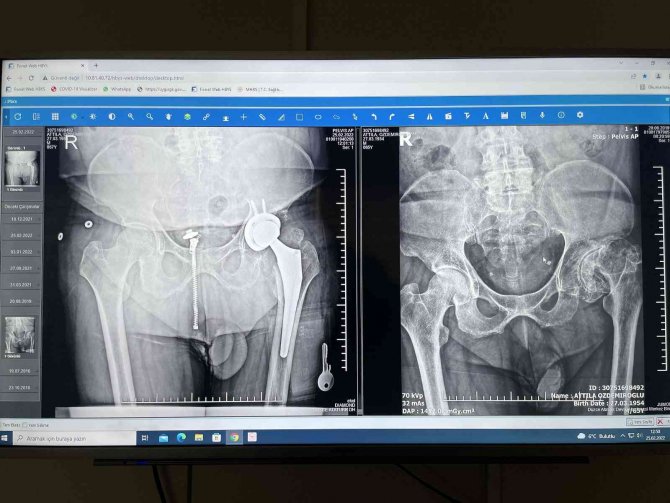

Düzce Atatürk Devlet Hastanesi'nde Ortopedi ve Travmatoloji Uzmanı olarak görev yapan ve uzmanlık eğitimini İstanbul Balta Limanı Kemik Hastalıkları Eğitim ve Araştırma Hastanesi'nde tamamlayan Op. Dr. Ömer Faruk Yılmaz, Attilla Özdemiroğlu'nun ameliyatını çok başarılı bir şekilde gerçekleştirdiklerini belirterek, ameliyatta yapılan çalışmaları anlattı. Yılmaz, "Attilla Özdemiroğlu ile geçtiğimiz sene göreve başladığım zaman tanıştık. Ameliyat ile ilgili düşüncelerimiz vardı. Pandeminin yoğunluğundan dolayı ameliyatını yapamıyorduk. 17 Aralık'ta kalça protezi ameliyatını yaptık. 46 yıl önce kalçasında geçirdiği enfeksiyondan dolayı kendisinde kısalık oluşmuştu. Onun hissettiği 4-5 santim ama röntgende ölçtüğümüz zaman 2.5-3 santimlik bir kısalığı vardı. Biz oradaki çürümüş olan kemiği çıkartarak, ona baş ve bir soket yapıp protez yaptık. Röntgen olarak 3 santimlik bir uzamamız oldu. Ama hastamızın hissettiği 4.5 santime kadar bir uzama var" dedi.